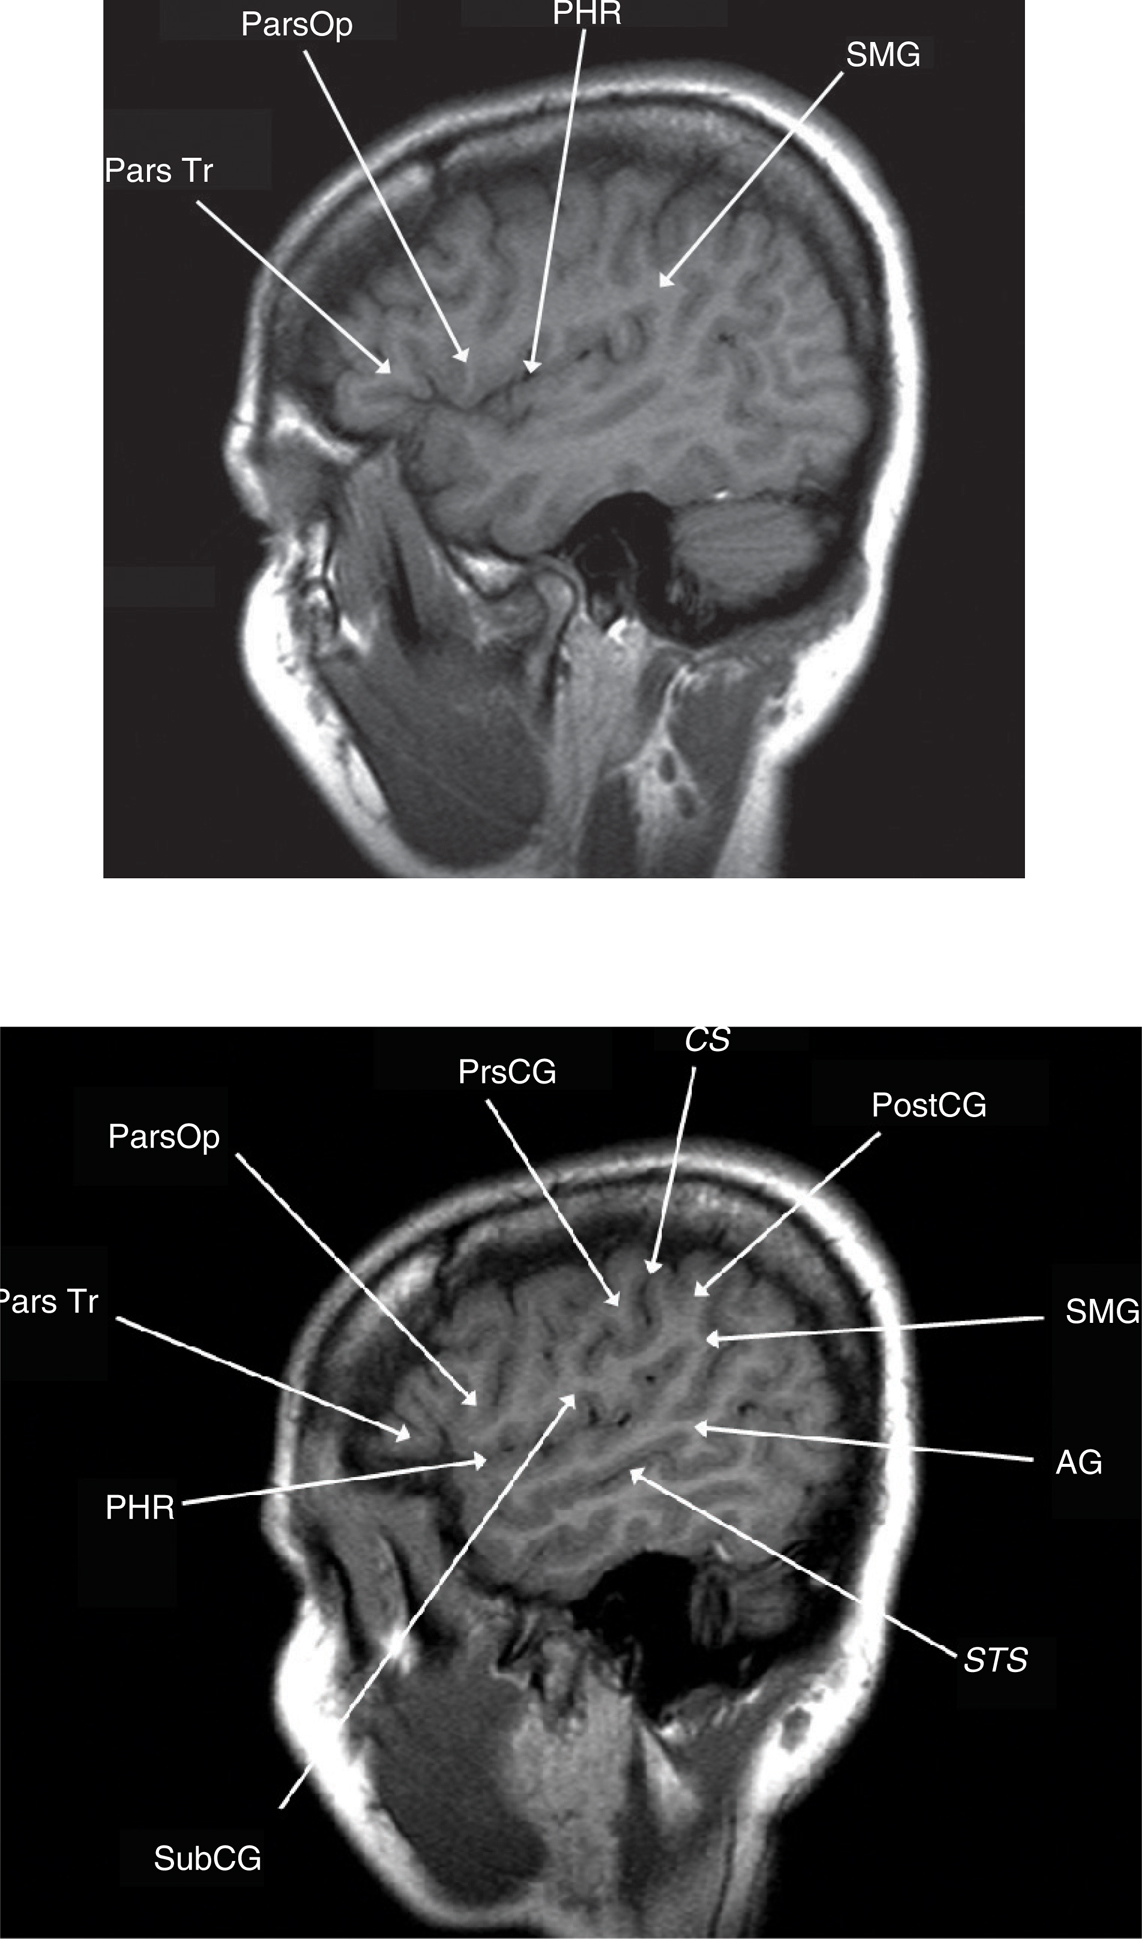

Cranial computed tomography (CT) has utility in presenting bone detail and the presence of calcification within a tumor bed. However, the anatomic detail provided by magnetic resonance imaging (MRI) is exquisite and provides cortical anatomical landmarks that are useful in preoperative planning. Relatively predictable patterns of sulci and gyri allow for identification of the primary sensory/motor cortices and speech centers. The concordance between MRI images and gross anatomical specimens has revealed “keys” for cortical landmark identification (4, 5). The first key is the Sylvian fissure and its five major rami. The posterior horizontal ramus (PHR) forms the main fissure that is visible on the convexity of the brain; it extends rostrally into the posterior ascending (PAR) and descending rami (PDR). The PAR is “capped” by the supramarginal gyrus (SMG). Anteriorly along the PHR, the sylvian fissure extends into two sulci, the anterior horizontal and anterior ascending rami. These rami extend into the inferior frontal gyrus (IFG) dividing it into the pars orbitalis, pars triangularis, and pars opercularis. The pars triangularis (Brodmann’s areas 45) and pars opercularis (Brodmann’s area 44) represent the primary motor or expressive speech area (Broca’s area).

The frontal lobe contains three gyri (superior, middle, inferior) separated by the superior and inferior frontal sulci. The superior frontal gyrus is appreciated on both axial and sagittal images (Figure 1). The middle frontal gyrus (MFG) extends posteriorly and fuses with the vertically oriented precentral gyrus. The precentral sulcus starts at midline and extends anteriorly and laterally in an oblique direction. The next key finding is the merging of the inferior frontal sulcus with the inferior ramus of the precentral sulcus, forming a “T” shape (4, 5). More posteriorly, the central sulcus is identified over the convexity on axial or sagittal images. It is oriented obliquely from posterior to anterior and does not extend all the way into the Sylvian fissure. Inferiorly, the precentral gyrus and postcentral gyrus merge under the central sulcus through a “U”-shaped gyrus (the subcentral gyrus). The post-central gyrus is characteristically narrower than the precentral gyrus (4, 5). Posteriorly, the Sylvian fissure is capped by the SMG, which is the anterior most portion of the inferior parietal lobule. Inferiorly, within the temporal lobe, coursing in parallel with the Sylvian fissure, is the superior temporal sulcus, which is capped posteriorly by the angular gyrus, the posterior limit of the inferior parietal lobule. The angular gyrus (Brodmann’s area 39) and posterior aspect of the superior temporal gyrus (STG) (Brodmann’s area 22) represent the primary receptive speech area (Wernicke’s area). The SMG (Brodmann’s area 40) contains fibers from the arcuate fasciculus that connect Wernicke’s and Broca’s areas (4, 5). The cingulate sulcus separates the cingulate gyrus from the medial aspect of the superior frontal gyrus. If followed posteriorly, the cingulate sulcus angles superiorly to form the pars marginalis, marking the posterior aspect of the paracentral lobule. The paracentral lobule houses the central sulcus, Broadman Areas 3,1,2 and 4,6. On axial images, the pars marginalis may be appreciated as a “bracket” (pars bracket) extending symmetrically from midline left and right. Anterior to this are the primary motor cortex and the postcentral sulcus. Areas 3,1,2 relate to the primary sensory cortex, and areas 4,6 include primary motor and supplemental motor areas (4, 5) (Figures 1 and 2).

Fig 3

Figure 3 Lateral sagittal T1-weighted MRI scans. Pars triangularis (Pars Tr), pars opercularis (Pars Op), posterior horizontal ramus of the sylvian fissure (PHR), and supramarginal gyrus (SMG). Subcentral gyrus (SCG), precentral gyrus (PCG), central sulcus (CS), postcentral gyrus (PoCG), supramarginal gyrus (SMG), angular gyrus (AG), and superior temporal sulcus (STS).